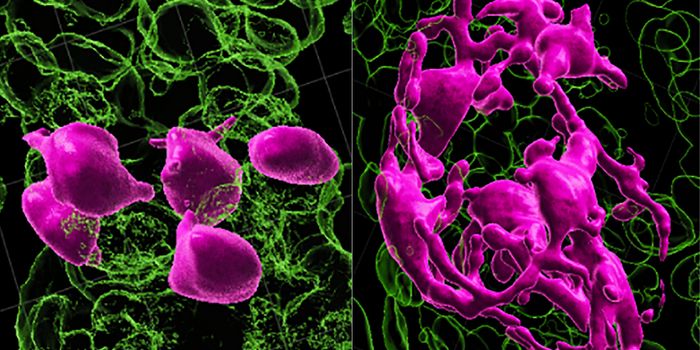

MAR 26, 2017Clinical & Molecular DXLab-grown red blood cells are not a new concept. But culturing enough of these cells in mass quantities was the main cha ...